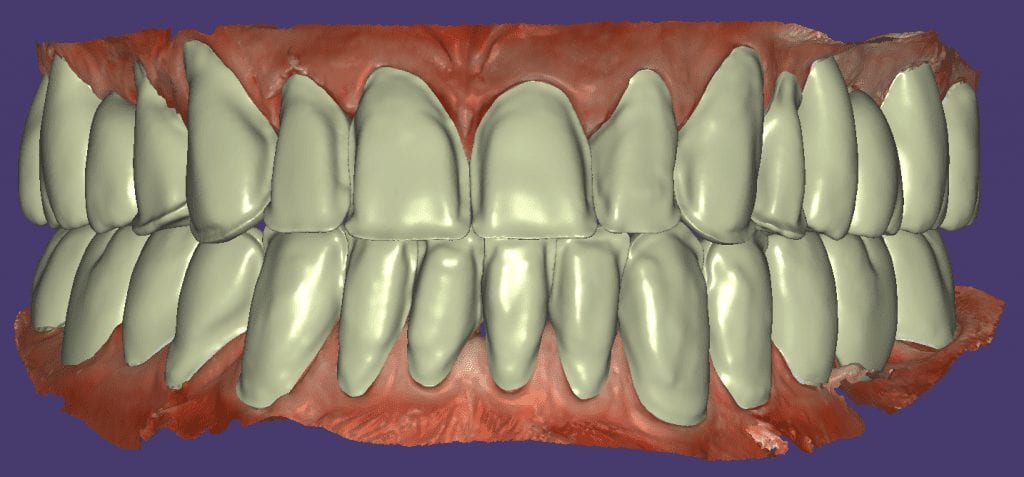

The initial vertical dimension was greater than desired and the tooth shape was too bulky in appearance.

Over the course of a few appointments, the vertical dimension was reduced and the temporaries were adjusted to the patient’s desires. The new upper and lower arch were captured with the Medit i500 and the jaws were related to each other.

This was then imported into exocad where the prepped arches from a few weeks prior were force matched to the new bite